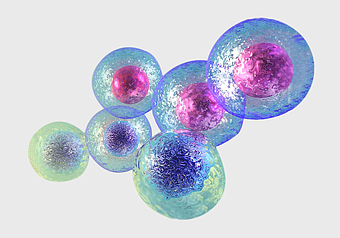

stem cell therapy benefits, umbilical cord blood cells, mesenchymal stem cell regeneration, hematopoietic stem cell treatment, cellular regenerative medicine, medical biotechnology advancements, purple cellular structures -